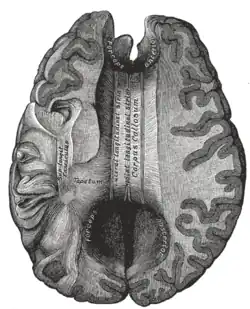

Ciało modzelowate

Ciało modzelowate, spoidło wielkie mózgu (łac. corpus callosum) – część mózgowia, najsilniej rozwinięte spoidło mózgu. Jest to pasmo istoty białej łączące dwie półkule mózgu. Położone jest na dnie szczeliny podłużnej mózgu.

Ciało modzelowate jest największym spoidłem mózgu, jego długość wynosi 7–10 cm. Na przekroju strzałkowym ma kształt podkowiasty. W jego obrębie wyróżnia się następujące części:

- pień ciała modzelowatego (truncus corporis callosi) – część środkowa spoidła;

- płat (splenium corporis callosi) – zgrubiała część tylna, przechodząca proksymalnie w pień;

- kolano (genu corporis callosi) – miejsce zagięcia pnia ciała modzelowatego ku dołowi w części bliższej spoidła;

- dziób (rostrum corporis callosi) – najbardziej proksymalna część tej struktury mózgu;

- blaszka dziobowa (lamina rostralis) – kończy dziób ciała modzelowatego.

Górna, wypukła powierzchnia ciała modzelowatego pokryta jest cienką warstwą istoty szarej, zwaną nawleczką szarą (indusium griseum). Pod nią biegną parzyste prążki podłużne, przyśrodkowe (striae longitudinales mediales) i boczne (striae longitudinales laterales). Poniżej ciała modzelowatego leży sklepienie (fornix); idąc od dołu, tkanka naczyniówkowa komory trzeciej, sklepienie i ciało modzelowate tworzą tzw. potrójny sufit komory trzeciej. Włókna komisuralne ciała modzelowatego biegną na boki powyżej komór bocznych mózgu, tworząc promienistość ciała modzelowatego (radiatio corporis callosi); włókna przednie kierują się do przodu jako tzw. kleszcze mniejsze (forceps minor), włókna części potylicznej promienistości ciała modzelowatego nazywane są kleszczami większymi (forceps major). Od obecności i przebiegu ciała modzelowatego w dużym stopniu zależy przebieg bruzd i zakrętów na przyśrodkowej powierzchni półkul mózgu.